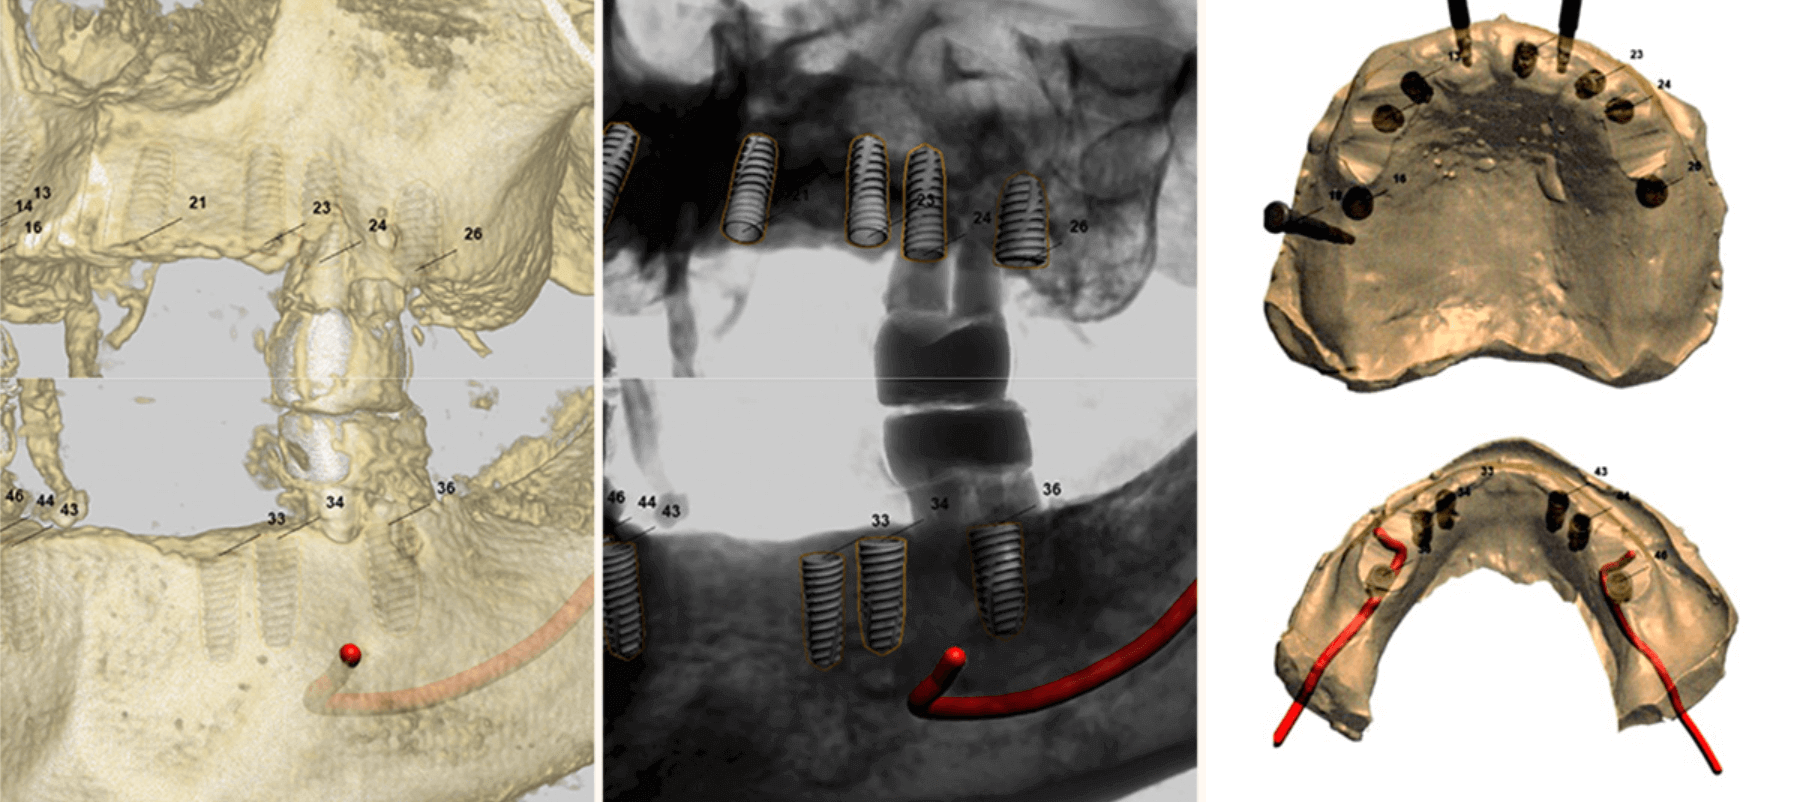

利用先進的數位診斷系統徹底分析患者的口腔狀況。

我們的目標是:僅在最準確的位置,放置最少數量的植體,以確保長期的穩定性與功能性。

模擬手術以判斷最佳的植體植入路徑